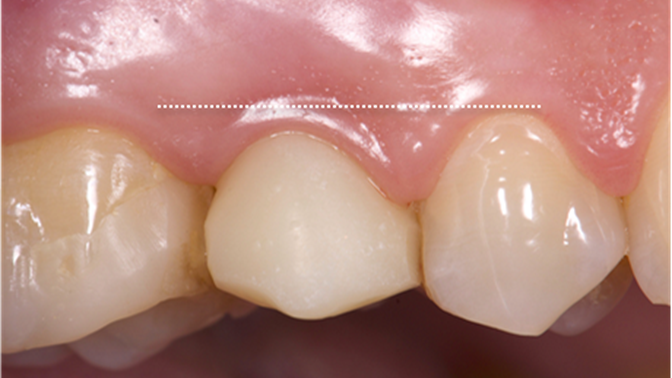

Clinical case: AnyRidge immediate loading

- Courtesy of Dr. Andres Paraud Freixas, Chile -

AnyRidge, ISQ value, initial stability, immediate loading, KnifeThread, maxillary anterior, Mega ISQ, Dr. Andres Paraud Freixas

Products:

AnyRidge implant system, Mega ISQ, Digital prosthesis

“Patient’s smile was recovered on the day of surgery

with reliable & highly-aesthetic results using AnyRidge & R2GATE. ”